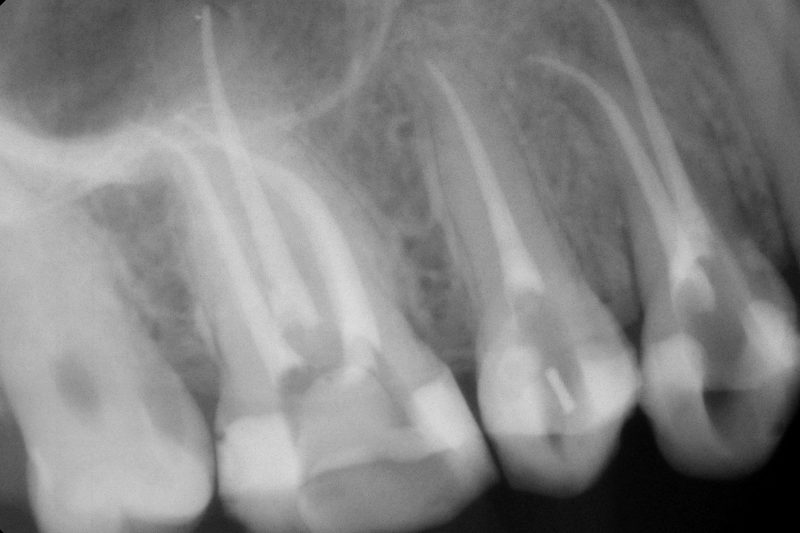

Контрольный рентген

Рентгенологический контроль заживления кости (через 3-6 месяцев)